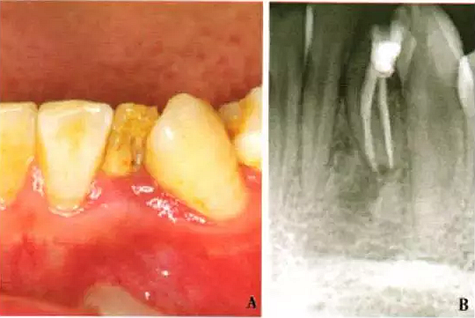

1周后,患者述疼痛消失。復診采用冷測壓方法根管充填(圖2),牙冠開髓孔處應用Chem—flex(DentsplyDeTreyGmbH,Konstanz,Germany)充填。由于患牙牙冠形態(tài)異常,且唇側(cè)形態(tài)尚未恢復;患牙周圍有牙石、軟垢,建議患者行牙周及修復治療以維持長期療效,被患者拒絕。9個月后隨訪,患者自述患牙經(jīng)治療后無癥狀,臨床檢查見32叩診正常,無松動;影像學檢查見32根尖周圍透射區(qū)域明顯減?。▓D3)。

A:32口內(nèi)像;B:X線片示32根尖周炎癥明顯減輕

圖3 左下側(cè)切牙9個月隨訪檢查